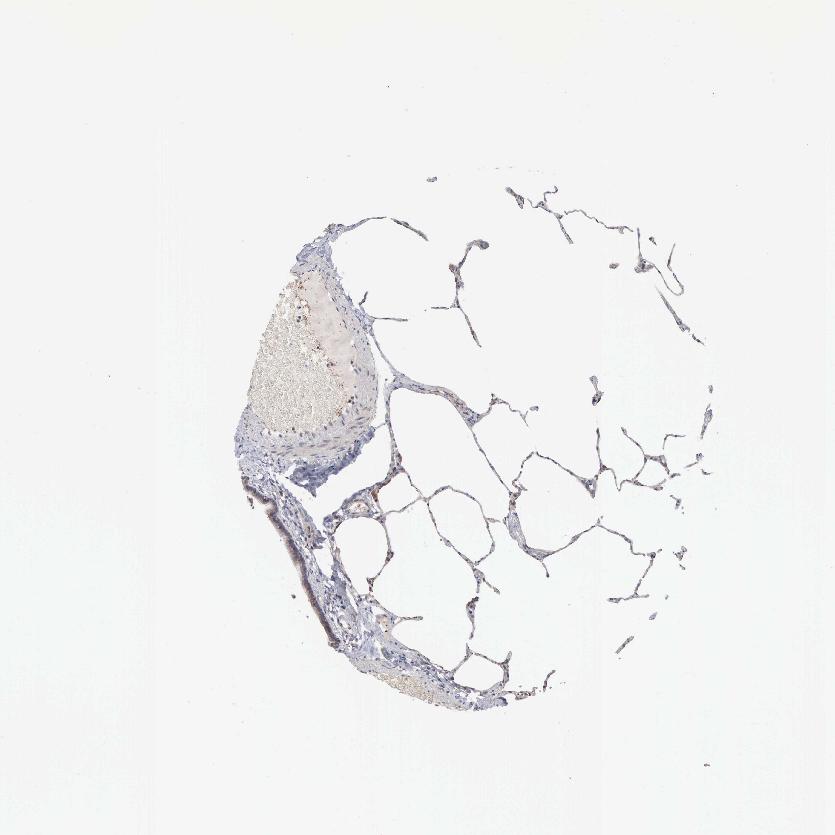

LUNG - Antibody stainingi

Antibody staining in the annotated cell types in the current human tissue is reported as not detected, low, medium, or high, based on conventional immunohistochemistry profiling in selected tissues. This score is based on the combination of the staining intensity and fraction of stained cells.

Each image is clickable and will lead to virtual microscopy that enables deeper exploration of all samples and also displays staining intensity scores, fraction scores and subcellular localization as well as patient and tissue information for each sample.

Antibody HPA000724

Alveolar cells Medium

Macrophages Medium